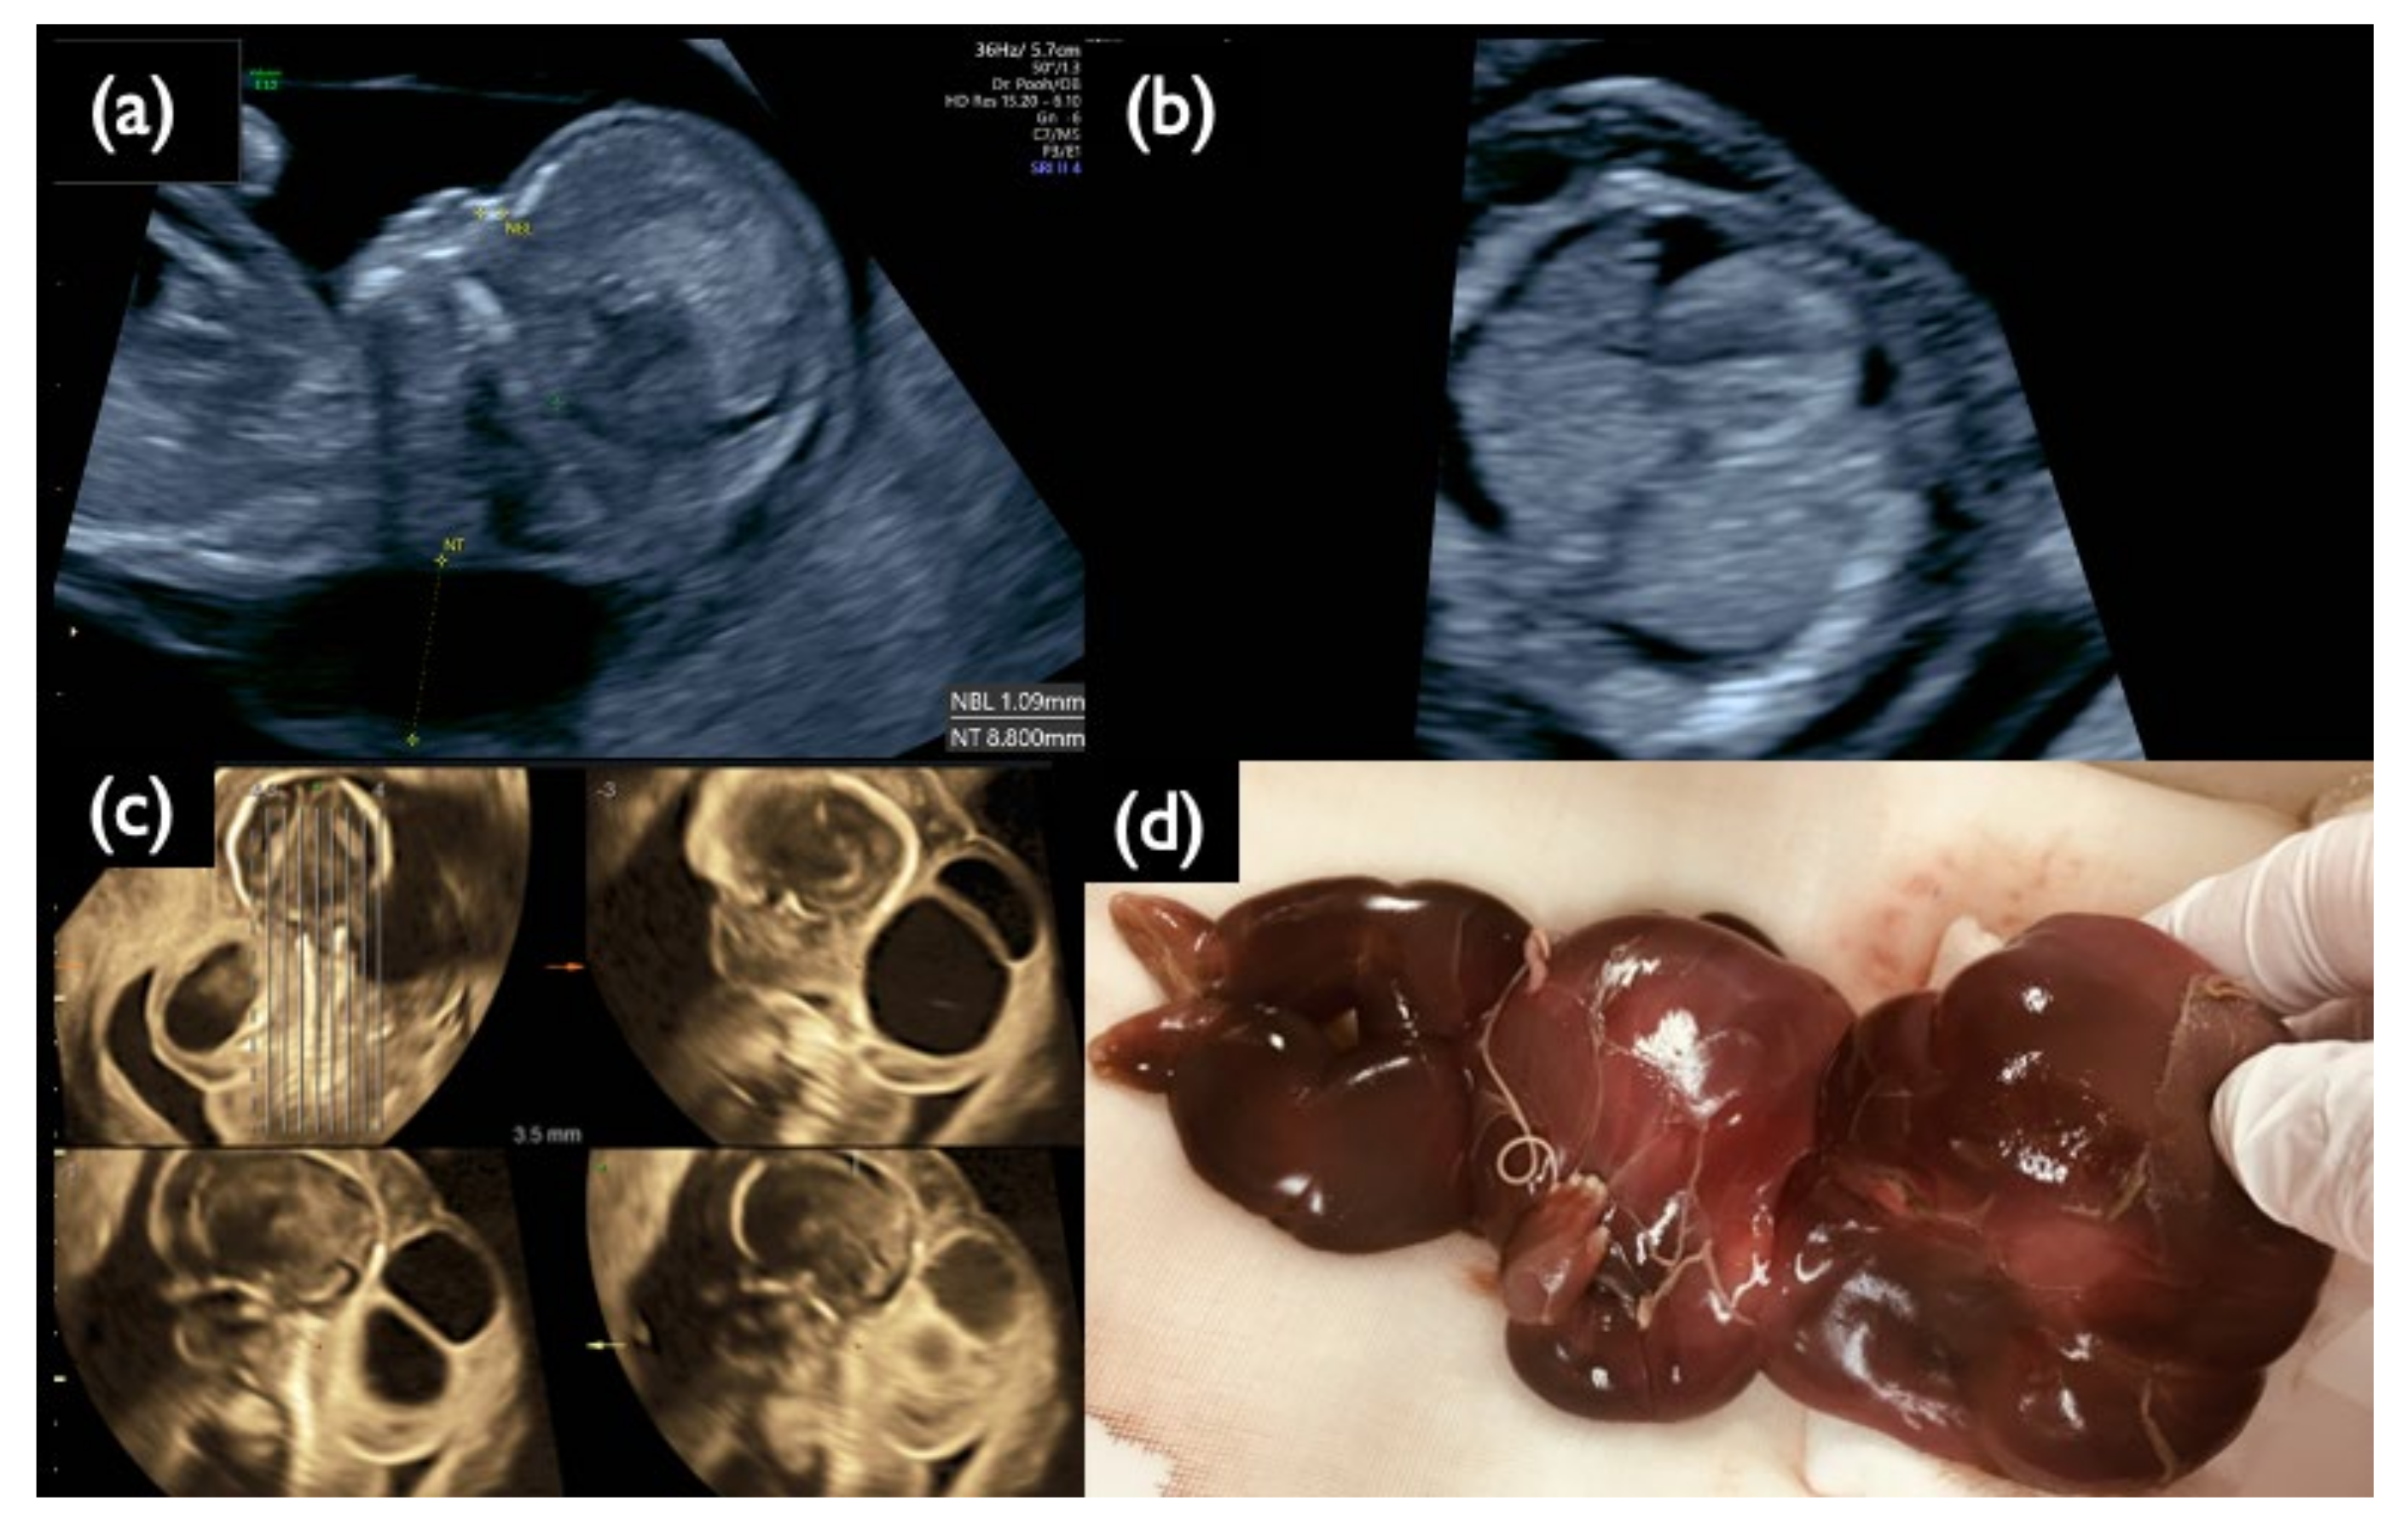

| Case | GA (Week + Day) for US and CVS | CVS | AC | CRITO–NIPT | Fetal Ultrasonography | |||||||

|---|---|---|---|---|---|---|---|---|---|---|---|---|

| QF–PCR | Uncultured FISH Aneuploidy (%) | G–Band Karyotype | Uncultured FISH Aneuploidy (%) | G–Band Karyotype | Result | Z–Score | Increased NT | NT Thickness (mm) | Sonographic Findings | |||

| Chromosome 21 relevant mosaicism | Mo1 | 13 + 3 | XY,+21 Mosaicism | T21 (96%) | 47,XY,+21 (100%) | – | – | T21 positive | 22.05 | + | 4.6 | Increased NT, GE very mild, Micrognathia, Lowset ear, DS like profile, Large VSD, TR moderate, Hyperechoic bowel, DV reverse, Tachycardia, Straight cord, T21 is strongly suspected |

| Mo2 | 13 + 2 | XX,+21 Mosaicism | Tetrasomy 21 (20%) | 49,XX,+7,+21,+21 /46,XX (72%/28%) | – | – | T21 Negative | 1.11 | – | 2.1 | Small NB, Lowset ear, TR moderate | |

| Mo3 | 13 + 0 | XXY | T21 (2%) | 47,XXY /48,XXY,+21 (62%/38%) | T21 (2%) | 47,XXY | T21 Negative | –0.48 | + | 3.4 | Increased NT, Small NB, TR mild, SUA, Genetic disorder is suspected | |

| Mo4 | 13 + 3 | XX,+21 Mosaicism | M21 (72%) T21 (8%) | 45,XX,–21 (100%) | M21 (1%) T21 (91%) | 46,XX,i(21)(q10) | T21 positive | 10.87 | + | 5.2 | Increased NT, Small NB, Micrognathia, Lowset ear, TR mild, DV defect, T21 is strongly suspected | |

| Chromosome 18 relevant mosaicism | Mo5 | 13 + 5 | XX,+18 Mosaicism | T18 (56%) | 47,XX,+18/46,XX (44%/56%) | – | – | T18 Negative | 2.09 | + | 8.3 | Increased NT, GE moderate, Small NB, Micrognathia, Lowset ear, T18 like profile, Wrist contracture bilateral, Cardiomegaly, Large VSD, TR severe, MR severe, Stomach invisible, Hyperechoic bowel, DV reversed flow, SUA, Umb.A.reverse, T18 is strongly suspected, |

| Mo6 | 13 + 0 | XY,T18 Mosaicism | T18 (88%) | 47,XY,+18 (100%) | – | – | T18 positive | 7.05 | + | 2.9 | Increased NT, NB defect, T18 like profile, Micrognathia, Lowset ear, Hypoplastic ear, Wrist contracture bilateral, Contracted lower extremities, Club foot (right), s/o DORV, RV>LV, TR moderate–severe, Omphalocele containing only bowel, DV reversed flow, FGR, T18 is strongly suspected | |

| Chromosome 13 relevant mosaicism | Mo7 | 12 + 3 | Normal XY | T13 (6%) | 46,XY (100%) | T13 (0%) | T13 (0%) | T13 Negative | 1.25 | – | 2.0 | TR mild |